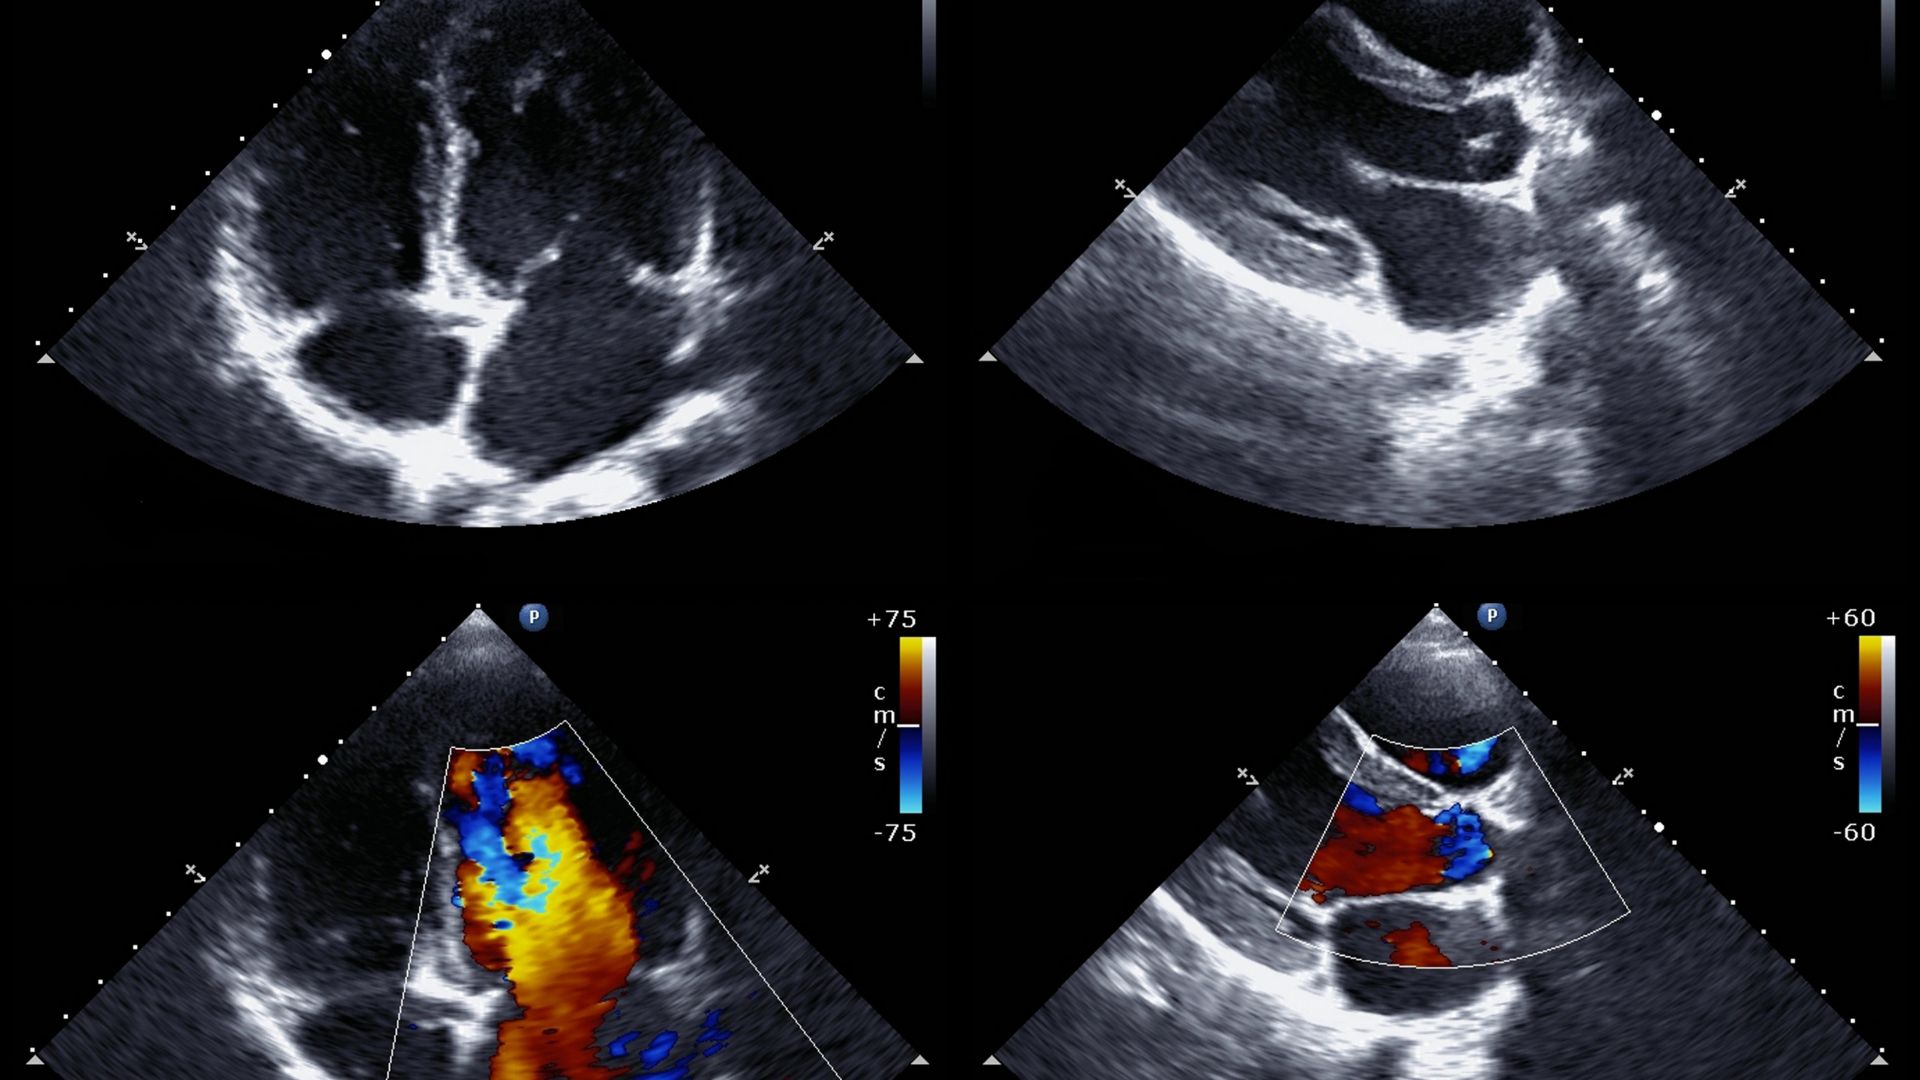

Siêu âm tim qua thực quản là phương pháp sử dụng sóng siêu âm với đầu dò được đưa qua đường miệng vào trong thực quản để thực hiện siêu âm, nhằm phát hiện nhiều bệnh lý của tim.

Theo bảng giá dịch vụ kỹ thuật khám chữa bệnh được Bệnh viện Tim Hà Nội cập nhật vào tháng 3/2024 trên trang web của bệnh viện, chi phí siêu âm tim qua thực quản có giá khoảng 900.000 VNĐ.